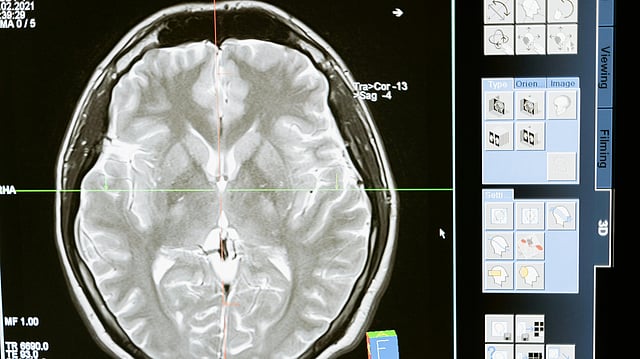

An MRI scan revealed a lesion in the frontal lobe of her brain, prompting urgent neurosurgical evaluation. This marked a turning point, as doctors suspected the disease had spread beyond the lungs and internal organs.